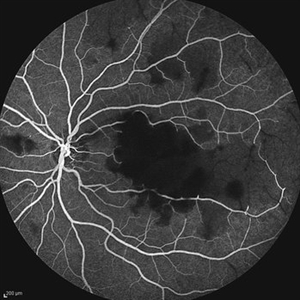

Idiopathic Occlusive Retinal Vasculitis (Late Stage) Idiopathic Occlusive Retinal Vasculitis (Late Stage)May 31 2014 by Hamid Ahmadieh, MD Wide- field image of the right eye of a 28-year-old woman with idiopathic occlusive retinal vasculitis 6 months after the onset. Photographer: Solmaz Shahmohammad, Negah Eye Center, Tehran Imaging device: Heidelberg Spectralis Condition/keywords: capillary closure, macular infarction

Idiopathic Occlusive Retinal Vasculitis (Late Stage) Idiopathic Occlusive Retinal Vasculitis (Late Stage)May 31 2014 by Hamid Ahmadieh, MD Late phase FA image of the right eye of a 28-year-old woman with idiopathic occlusive retinal vasculitis 6 months after the onset. Photographer: Solmaz Shahmohammad, Negah Eye Center, Tehran Imaging device: Heidelberg Spectralis Condition/keywords: capillary closure, fluorescein leakage, macular infarction

Idiopathic Occlusive Retinal Vasculitis (Late Stage) Idiopathic Occlusive Retinal Vasculitis (Late Stage)May 31 2014 by Hamid Ahmadieh, MD Late phase FA image of the right eye of a 28-year-old woman with idiopathic occlusive retinal vasculitis 6 months after the onset. Photographer: Solmaz Shahmohammad, Negah Eye Center, Tehran Imaging device: Heidelberg Spectralis Condition/keywords: capillary closure, macular infarction